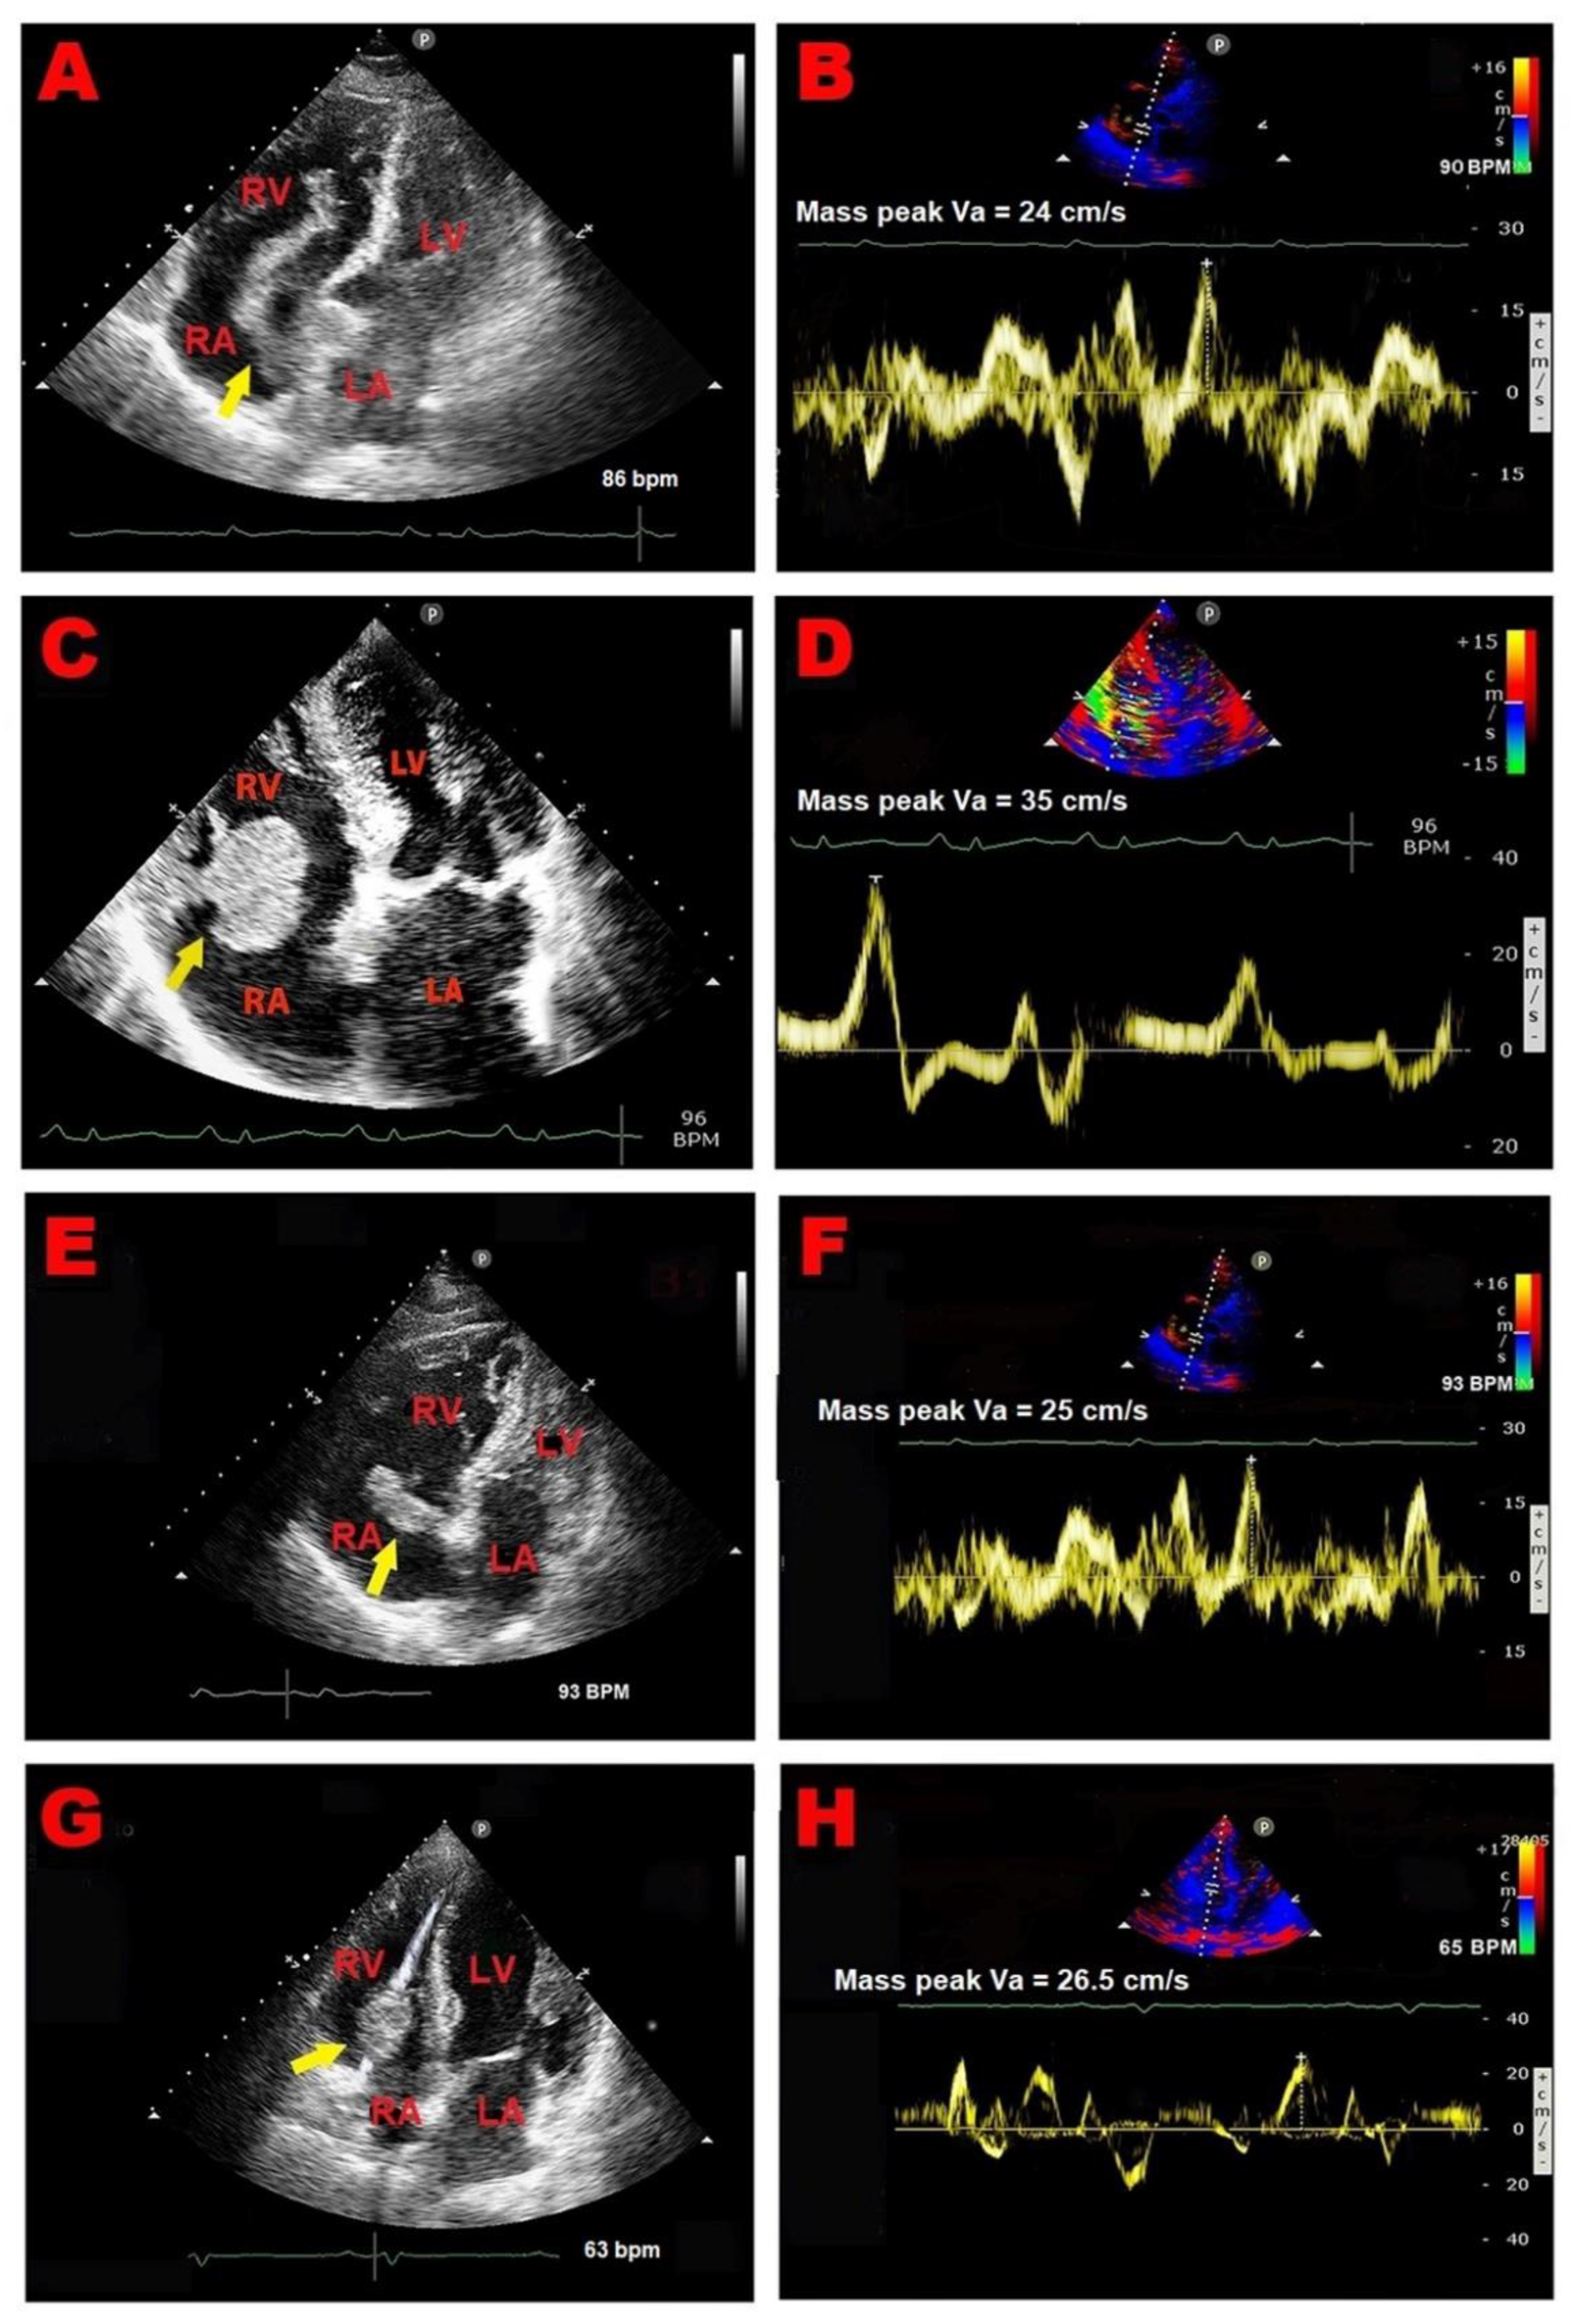

2.1. Clinical Case 1

2.2. Clinical Case 2